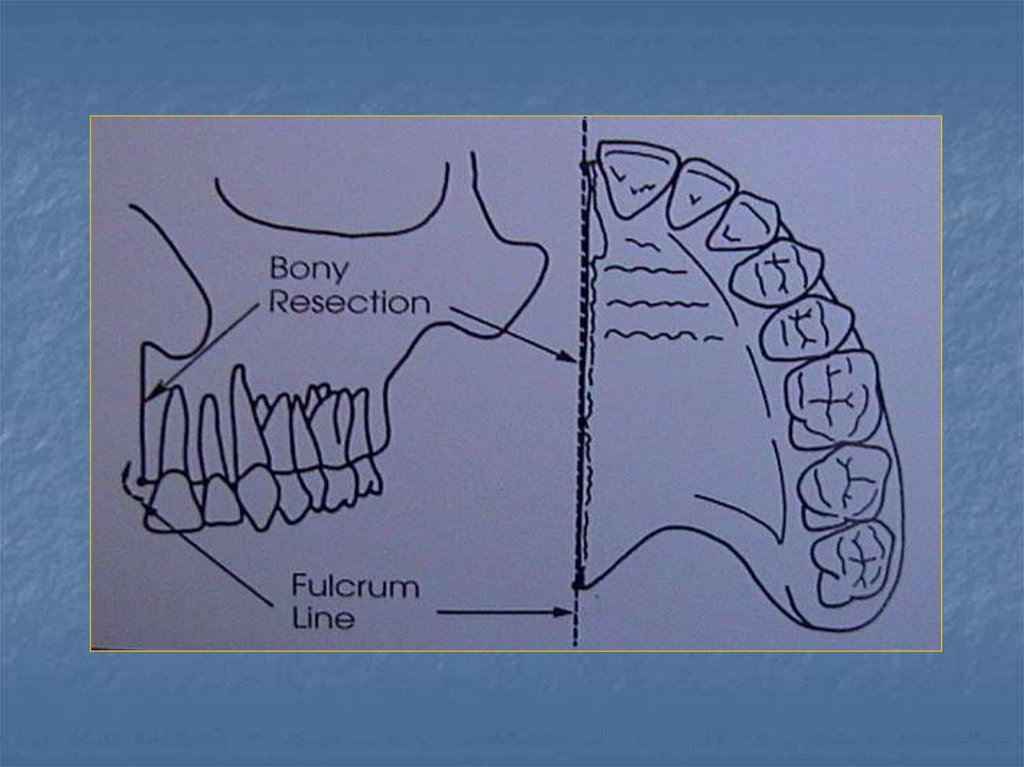

39. Stabilite

Protezin yatay düzlem

etrafındaki rotasyonu

fullkrum çizgisi

etrafında görülen

rotasyondur.

obtüratör planlaması,

retansiyon ve

stabiliteyi birlikte

sağlamaya yönelik

yapılmalıdır.

36. 5- Yan duvar yüksekliği

Defektin yan duvarı endirekt retansiyon için

kullanılabilir. Defektin yan duvarı obturatörün

arksal yer değiştirmesi ile oluşan basınca karşı

direnç oluşturur. Protezin defekt içindeki

retansiyonu "fulkrum" noktasını merkez kabul

eden ve bir yarı çap boyunca sürüklenen bir

noktanın dikey yer değiştirmesi ile meydana

gelir. Obturatörün yan duvar yüksekliği artırılırsa

protezin yer değiştirmesi (rotasyonu ) azaltılır.